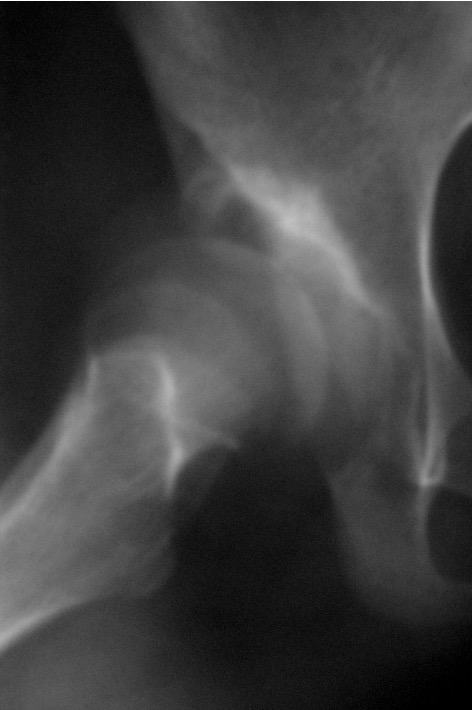

Xray

Dislocated hips in the setting of DDH with ncreased acetabular index